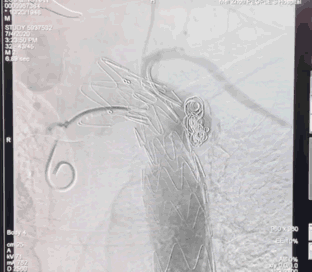

3228-200胸主动脉支架定位

胸主动脉支架释放后造影

由于患者年龄较大,主动脉严重缩窄合并主动脉瘤,主动脉结构较为脆弱,所以李存仁教授决定在胸主动脉覆膜支架植入后再对缩窄部位进行球扩。这样,已经植入的支架能够起到一定的保护作用,在支架的限制下,球囊既充分扩开了狭窄部位,又避免了过度扩张对主动脉造成的损伤。

使用球囊28mm*40mm扩张

植入弹簧圈进行填充封堵内漏